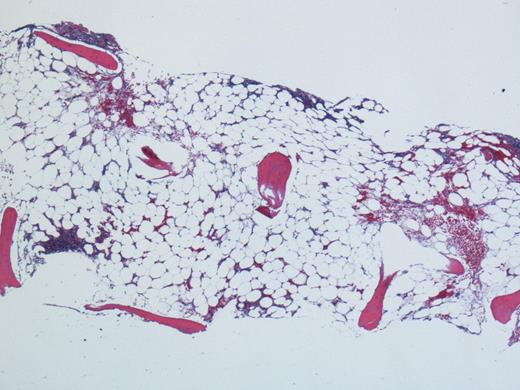

A 42 y/o male presented to the emergency department with 3 weeks history of fatigue and epistaxis. On initial blood work he was found to have pancytopenia with hemoglobin of 4.7g/dl, platelet count of 4,000 and absolute neutrophil count of 160. He has no significant family history. His past medical history was only significant for a skin rash, which was biopsied 3 months ago and reported to be follicular dermatitis. The only home medication he has taking was doxycycline 100mg twice a day for the past few weeks before the current hospital admission. He was transfused with packed red blood cells and platelets to maintain hemodynamic stability. His bone marrow biopsy was reported to be hypocellular (<5% cellularity) with normal morphological features (see figure 1). Paroxysmal nocturnal hemoglobinuria was ruled out by flow cytometry. Workup including HIV, EBV, Hepatitis B and C and parvovirus serology was reported to be negative. His history of long-term Doxycycline use as well as no family history of any similar disorder, it is plausible that doxycycline could have caused his aplastic anemia. In congruence with the above mentioned findings, he is diagnosed with very severe aplastic anemia and is planned to be started on immunosuppressive therapy with equine anti-thymocyte globulin and cyclosporine along with consultation for allogeneic transplant.

Hypo-cellular Bone Marrow